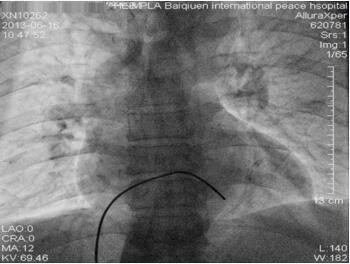

给予盐酸替罗非班静脉泵入,RCA植入支架(2.5mm × 23mm Xience V支架),血流恢复(图1-23-5)。冠状动脉造影及支架手术顺利,患者胸闷症状缓解。术后12小时出现间断起搏不良,床旁非透视下微调起搏电极后起搏功能恢复正常。术后24小时再次出现起搏功能不良,导管室透视下与前一天临时起搏电极位置(图1-23-6)比较,发现心室起搏电极头端在右室心尖部较前有移位,位置较深(图1-23-7),遂撤出电极导线将起搏电极导线重新调整定位,起搏感知功能良好,起搏频率50次/分,观察血压正常,回到监护病房。

图1-23-6 临时起搏电极位置(急诊)